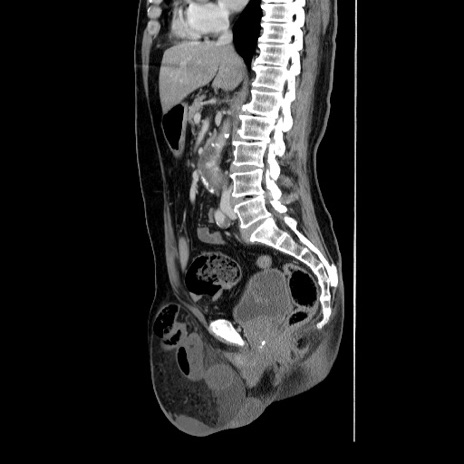

横断像

【症例】60歳代 男性

【主訴】右鼠径部膨隆

【現病歴】1年程前より右鼠径部膨隆あり。自己にて還納可能だったため放置していた。3時間前より右鼠径部の脱出を認め、還納困難となり受診。

【身体所見】右鼠径部に小児頭大の膨隆あり。弾性硬であり、用手還納は困難。左鼠径部にも膨隆を認める。脱出はなし。